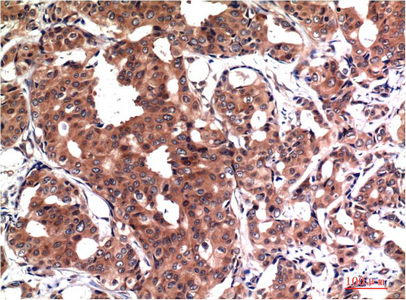

- Immunohistochemistry analysis of paraffin-embedded Human Breast Carcinoma Tissue using GSK3 beta antibody.High-pressure and temperature Sodium Citrate pH 6.0 was used for antigen retrieval.